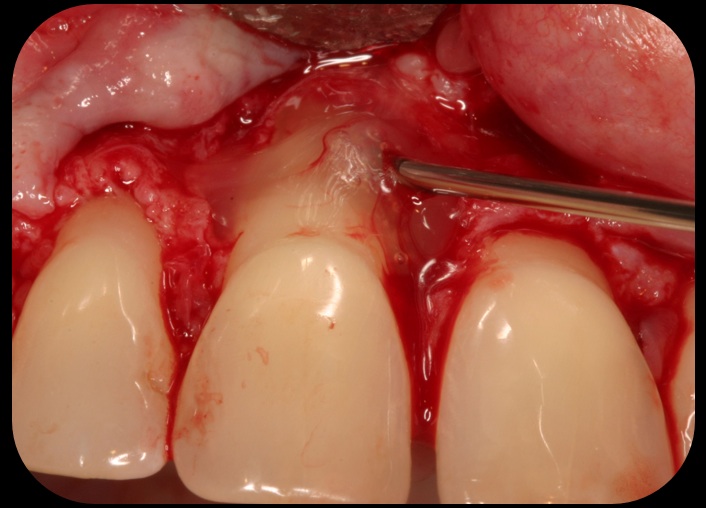

Application of enamel matrix derivative.

Fig. 4

Then, too, are opportunities to prepare the site for regeneration by coupling therapies, applying an enamel matrix derivative, along with traditional bone grafts of demineralized freeze-dried bone allograft; potentially, gains in attachment with minimal probing depth and retained papilla may avoid the need for an implant (Figure 2 through Figure 7).